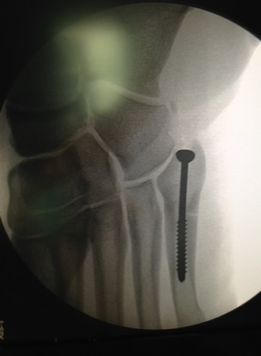

Полузащитникът на Реал Мадрид Чаби Алонсо има имплантиран пирон в малкото пръстче на десния крак, разкри вестник "АС". Баският халф беше опериран в четвъртък след фрактура на петата метатарсална кост. Според медиците вкраването на пирон е нормална процедура при такива контузии и цели стабилизиране на ходилото.

Интервенцията за вмъкване на чуждото тяло обикновено продължава около половин час. По принцип пиронът може да продължи да стои в крака на човек цял живот, като се създават трудности само при обуване на обувки. Алонсо получи същата контузия преди 12 години, но тогава на левия крак. Очаква се да отсъства от терените между два и три месеца.